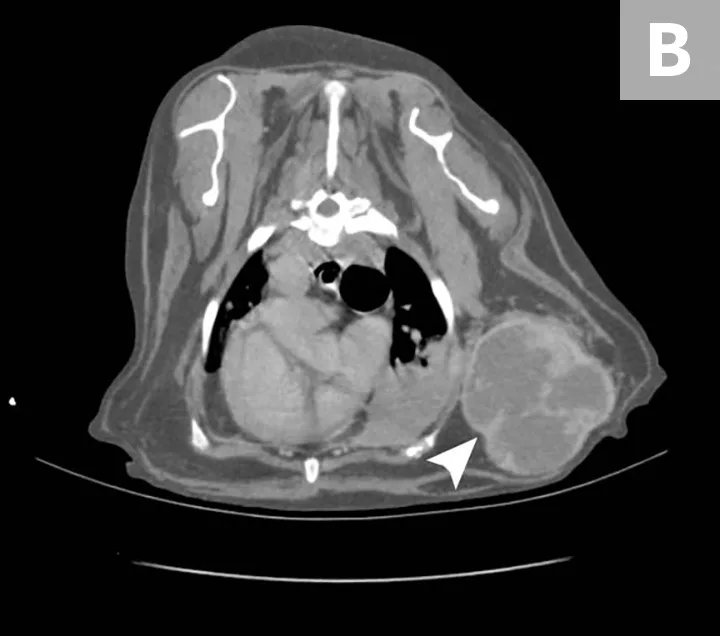

Although HSA can be presumptively diagnosed based on multiple clinical and physical findings and patient signalment, baseline diagnostic tests (see Baseline Diagnostic Tests) should be considered in patients that have probable HSA. Detailed images of HSA lesions arising from visceral organs, SC tissue, and deeper muscle structures can be acquired with advanced imaging modalities (eg, CT; Figure 3).

CT images of primary splenic HSA (A, arrowhead), SC HSA (B, arrowhead), and deep-muscle HSA (C, arrowhead). Figures courtesy of Louis-Philippe de Lorimier, DVM, DACVIM (Oncology)